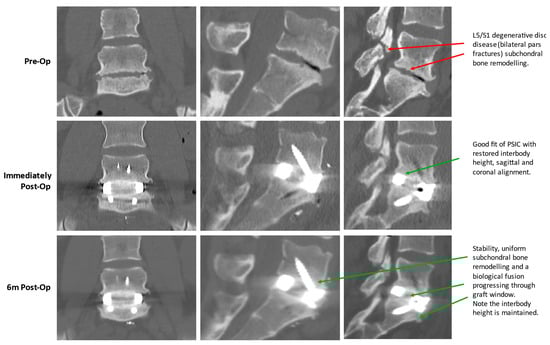

4.4. Efficacy